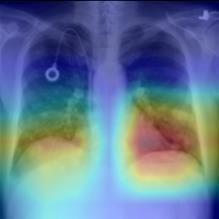

Thoracic disease detection from chest radiographs using deep learning methods has been an active area of research in the last decade. Most previous methods attempt to focus on the diseased organs of the image by identifying spatial regions responsible for significant contributions to the model's prediction. In contrast, expert radiologists first locate the prominent anatomical structures before determining if those regions are anomalous. Therefore, integrating anatomical knowledge within deep learning models could bring substantial improvement in automatic disease classification. This work proposes an anatomy-aware attention-based architecture named Anatomy X-Net, that prioritizes the spatial features guided by the pre-identified anatomy regions. We leverage a semi-supervised learning method using the JSRT dataset containing organ-level annotation to obtain the anatomical segmentation masks (for lungs and heart) for the NIH and CheXpert datasets. The proposed Anatomy X-Net uses the pre-trained DenseNet-121 as the backbone network with two corresponding structured modules, the Anatomy Aware Attention (AAA) and Probabilistic Weighted Average Pooling (PWAP), in a cohesive framework for anatomical attention learning. Our proposed method sets new state-of-the-art performance on the official NIH test set with an AUC score of 0.8439, proving the efficacy of utilizing the anatomy segmentation knowledge to improve the thoracic disease classification. Furthermore, the Anatomy X-Net yields an averaged AUC of 0.9020 on the Stanford CheXpert dataset, improving on existing methods that demonstrate the generalizability of the proposed framework.